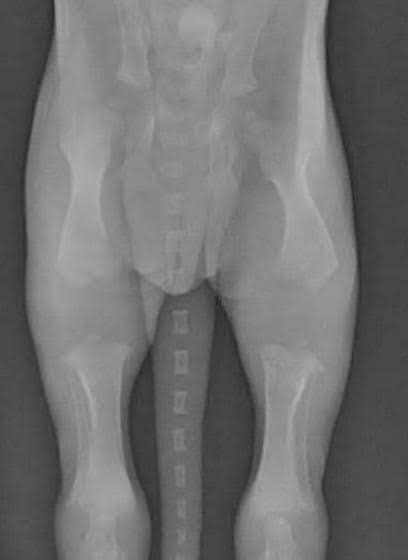

Growth plates (also called epiphyseal plates) are soft areas of cartilage located at the ends of long bones. As your puppy matures, these plates slowly harden (calcify) and turn into solid bone.

For healthy development, bones must grow evenly and at the same rate. This synchronized growth is critical for producing correct structure, balance, and movement — especially in powerful, muscular Bully breeds.

Until the growth plates fully close, they remain vulnerable to injury. They are actually the last part of the bone to harden.

One of the most common areas for growth plate issues is between the radius and ulna in the front leg. If one bone stops growing and the other continues, it can result in bowed legs and an abnormal gait that affects the dog permanently. Over time, this imbalance can place stress on other joints and lead to secondary issues such as arthritis or ligament strain.

X-Ray of a puppy